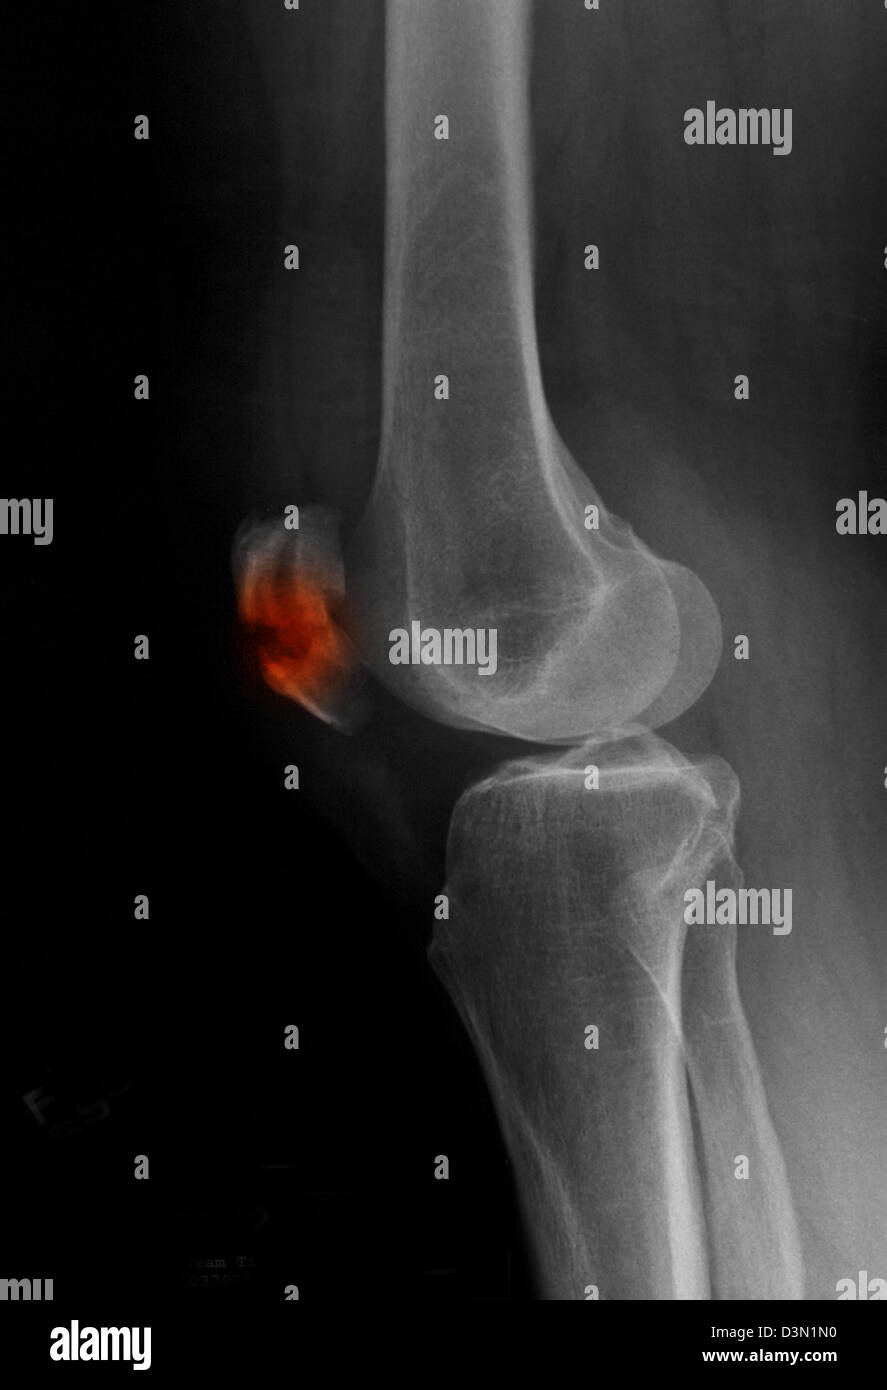

From www.alamyimages.fr

Fracture de la rotule Banque d'images noir et blanc Alamy Fracture De La Rotule la fracture de la rotule est une lésion osseuse fréquente suite à une chute sur le genou. Elle nécessite souvent une chirurgie pour rétablir l'extension du genou et prévenir l'arthrose. La rééducation doit démarrer le plus tôt possible pour éviter que l’articulation s’enraidisse. la fracture de la rotule est une blessure grave qui nécessite souvent une intervention chirurgicale. Fracture De La Rotule.